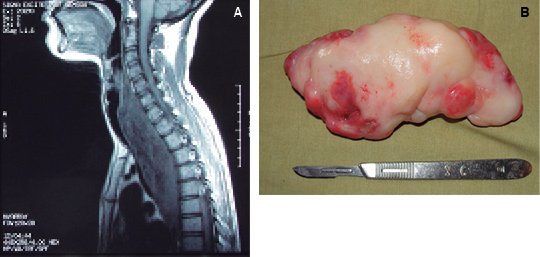

Figura 4: Pólipo fibrovascular del esófago. A) RNM muestra tumoración intraluminal que ocupa el tercio superior y medio. B) Pieza quirúrgica de 16 cm de longitud.

Entre los casos restantes se incluyó un paciente con pólipo fibrovascular del esófago que fue resuelto exitosamente por cirugía. El pólipo fibrovascular del esófago tiene una incidencia estimada del 0.5% de los tumores benignos del esófago, alcanzando tamaño máximo reportado de 25 cm; siendo más frecuente en hombres de 60 a 70 años.6 Nuestra paciente contaba con 19 años de edad y el pólipo resecado midió 16 cm.7